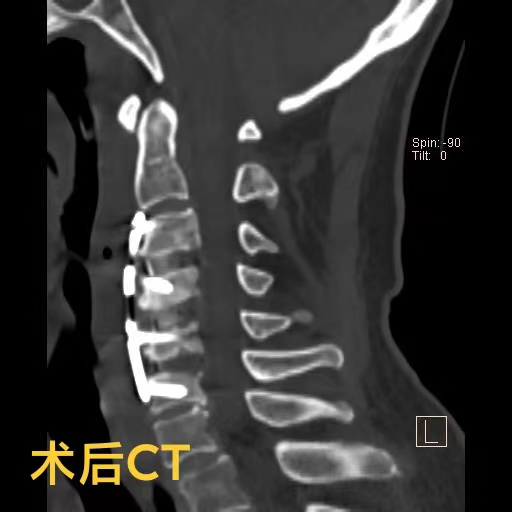

陈爷爷长期的颈椎变形产生了大量骨质增生,给术中的邓雷、蒋登志医生出了难题。在神经显微镜下,他们的眼睛如鹰,指尖之中飞舞最温柔的神经刀锋,雕塑着最坚硬的颈椎骜骨。最终,手术耗时两个半小时,成功矫正,没有神经损伤!患者术后3天康复出院。